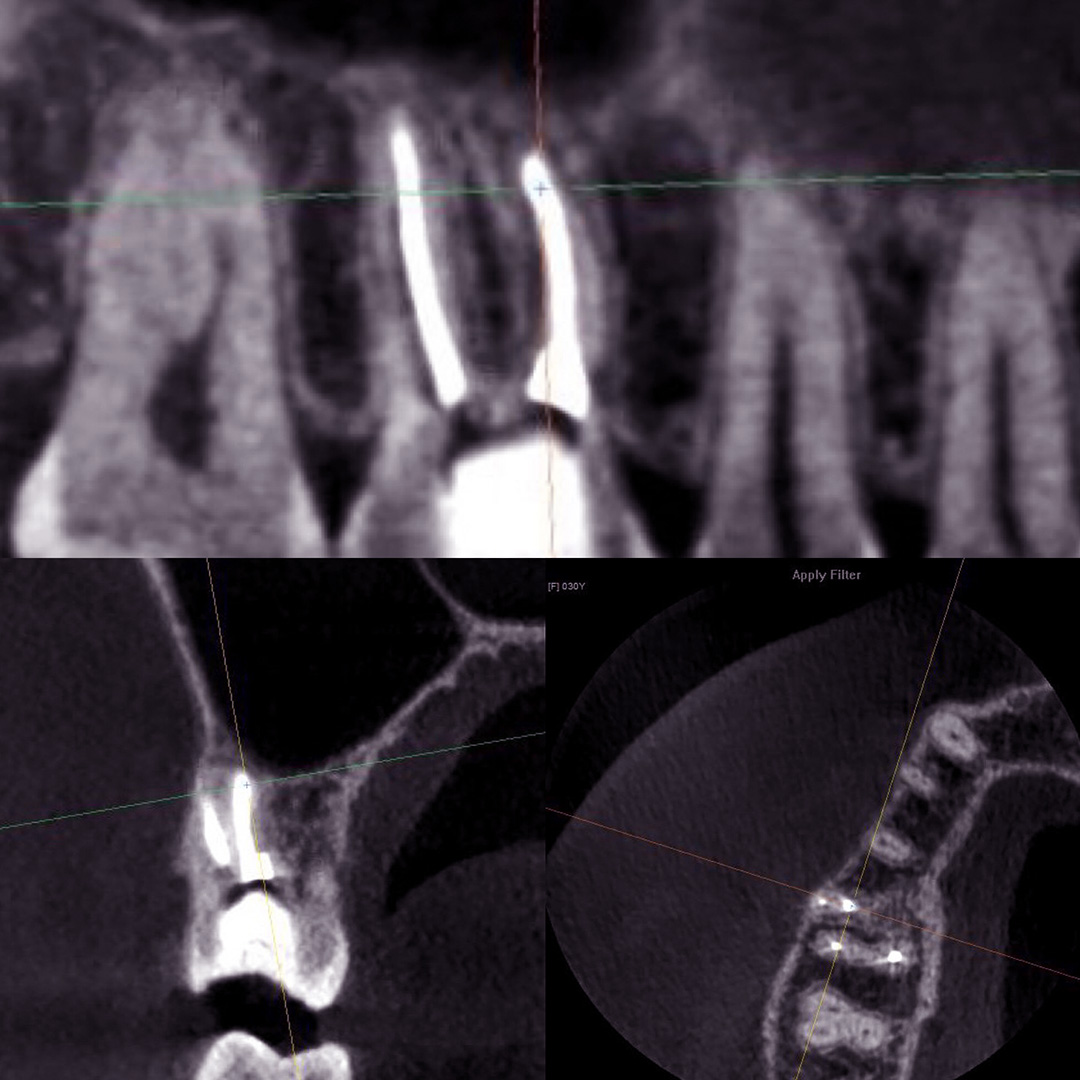

Пациентка после лечения в другой клинике обратилась в «Стоматологию Комфорта» с жалобами на ноющие боли в области жевательных зубов верхней челюсти. Боли усиливались при принятии пищи и горячих напитков. В результате проведения конусно-лучевой компьютерной томографии врач Вахлюева Елена Сергеевна обнаружила пропущенный дополнительный канал в ранее леченом моляре. Проведено селективное эндодонтическое лечение с пломбированием зуба.

Лечение включало следующие мероприятия:

- проведение конусно-лучевой компьютерной томографии и выявление проблемы;

- селективное эндодонтическое лечение зуба 1.6;

- пломбирование канала зуба.